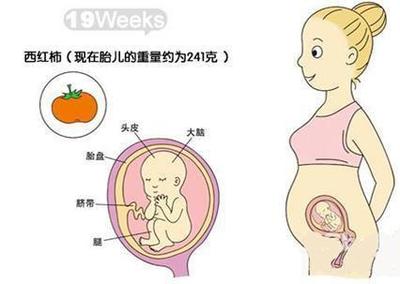

怀孕五个月的时候,你已经走完了怀孕的一半路程。下面说说怀孕五个月时的胎儿大小和发育情况。怀孕5个月时的胎儿大小(图)怀孕第五个月的第一周,胎儿大小约14cm,体重约200克;怀孕第五个月第二周,胎儿大小15cm左右,体重200,250g。怀孕第五个月第三周,胎儿大小约1516cm,体重约260克。怀孕第五个月第四周,胎儿大小约18cm,体重300,350克。

胎儿大小约19cm,体重约350克。怀孕第五个月底,胎儿大小约17.522.5cm,胎儿体重接近0.5 kg。这个月底,宝宝的耳朵发育良好,可以开始分辨声音了。所以妈妈可以给宝宝讲故事,或者听一些幼儿歌曲。这个月,宝宝和我们成年人一样,有规律的睡眠和清醒期。会做鬼脸。如果是男宝宝,那么宝宝的睾丸已经开始从腹腔下降到阴囊了。

怀孕五月的这个时候,胎儿已经进入快速生长发育阶段。因此,孕妈妈此时应遵医嘱控制饮食,少吃淀粉,多吃蛋白质,蛋白质中维生素含量高,有助于胎儿的生长发育。这个时候宝宝已经是柚子大小了。宝宝在妈妈肚子里一天天长大,5月份胎儿长得更快,变化明显,妈妈能感觉到胎动。对于准妈妈来说,这是多么甜蜜的负担啊。宝宝每月体重多少才算健康?

接下来,我们来看看五个月大的胎儿是什么样的水果。五个月大的胎儿长什么样?五个月大的胎儿就像一个苹果。怀孕第17-20周是怀孕的五月。在这个阶段,胎儿生长迅速,变化明显。这个月,子宫在腹腔内逐渐增大。此时可在耻骨联合上方约1518 cm处测量子宫底的高度和厚度。当宝宝19周大时,孕妇的子宫底部每周会上升1厘米。孕16周结束时,胎儿皮肤红润透明,可见皮下血管。根据外生殖器,可以区分男性或女性(借助超声波);呼吸肌开始运动;1个月后皮肤逐渐变得暗红不透明,开始长出胎毛、胎毛、眉毛、指甲。

很多孕妇在怀孕期间,尤其是怀孕中后期,可能会幻想自己的宝宝长什么样。做b超的时候,他们可以清楚地看到宝宝的各个部位。孕妇看到肚子里的胎儿,会有莫名的幸福感。怀孕五个月后的胎儿是什么样的?怀孕5个月后胎儿多大?1.怀孕五个月的胎儿图片胎儿在此期间的成长是惊人的,身长18-22厘米,体重250-300克。细毛(毛发)长满全身,头发、眉毛、指甲都准备好了。

头重脚轻的身体被分成三部分,最后称重。皮肤逐渐呈现出漂亮的红色,皮下脂肪开始平复,逐渐变得不透明。因为皮下脂肪少,所以不会长得很胖。随着骨骼和肌肉的强壮,手臂和腿部的活动变得活跃,然后会感觉到明显的胎动。心脏的活动也是活跃的,可以听到强有力的心音。2.怀孕五个月后的胎儿b超。怀孕五个月后的胎儿头部已占全身长度的三分之一,耳朵的入口是敞开的;牙龈开始形成;皮肤红润透明,可见皮下血管;开始长出胎毛,胎毛,眉毛,指甲。

怀孕5个月,也就是17周,胎儿长约1825厘米,重约250300克,差不多有一个苹果那么大。怀孕第17周,胎心发育基本完成,心跳强烈,约145次/分钟。准妈妈可以借助听诊器听到胎儿强有力的心跳。胎儿强有力的心跳可以减少准妈妈生孩子的恐惧,增加她们的信心。胎儿的循环系统和尿道完全处于正常工作状态,肺部也开始工作。

大部分准妈妈都开始感觉到胎动了。此时,胎儿大脑发育趋于完善,脑神经元的树突形成,最原始的意识开始出现。小脑半球也开始形成,但延髓以上的中脑还没有发育好。因此,胎儿不具备支配运动的能力,对外界刺激不够敏感。准妈妈要注意保护。五个月的胎儿全身比例匀称,皮肤比以前更红,眉毛细长,眼睛更大,鼻孔更大,嘴巴更窄,牙齿更好看,脖子更长。

怀孕五个月是指怀孕17 ~ 20周。此时胎儿身高20~25厘米,体重250~300克。全身长满了细毛,头发也开始长了,眉毛和指甲也整齐了。头的大小就像一个鸡蛋。头重脚轻的身体分成三部分,身体的比例最终显得匀称。皮肤逐渐出现红色,皮下脂肪开始平复,皮肤变得不透明。胎儿心跳非常活跃,胎儿手脚可以在羊水中自由活动。

怀孕五个半月的胎儿有多大?孕期饮食要清淡,这样才能保证营养均衡。其实胎儿的发育是可以根据自身的身体状况来观察的。那么怀孕五个半月的胎儿有多大呢?我来介绍一下怀孕五个半月的胎儿有多大。怀孕五个半月的胎儿有多大?1.怀孕五个半月,也就是我们常说的2022周的时期。准确的说,孕妈妈进入这个月,已经避开了容易流产的危险期,进入了相对安全的孕中期。

从怀孕五个月的b超图像中,可以清楚地看到胎儿的耳朵已经微微张开,头发和眉毛已经开始生长,牙龈也开始形成。手指和脚趾开始鼓胀,长出指甲。有时候,他喜欢把手放进嘴里,感觉手上的味道是人间美味。一般来说,五个半月的胎儿体重在250克左右,而身高在16.517cm左右,双顶径平均4.88 cm,腹围平均14.80 L。